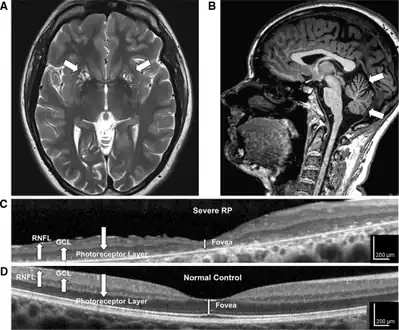

a-d)High-resolution retinal and brain imaging in NARP syndrome demonstrates analogous patterns of tissue injury